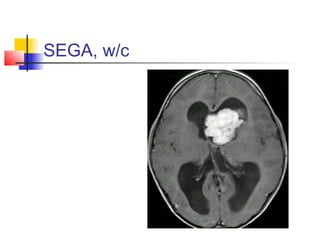

4. SUBEPENDYMAL GIANT CELL

ASTRCYTOMAS (SEGA)

 Mostly in patients with tuberous sclerosis.

 Usually benign, slowly growing, and arise near

the foramen of Monro.

 Found incidentally or because of

hydrocephalus.

 Imaging: hyperdense, hyperintense, with

calcification, and enhanced.

 Treatment is indicated if it grows or causing

SEGA, w/c

Masses of thelateral cerebral ventricle 4. SUBEPENDYMAL GIANT CELL ASTRCYTOMAS (SEGA)  Mostly in patients with tuberous sclerosis.  Usually benign, slowly growing, and arise near the foramen of Monro.  Found incidentally or because of hydrocephalus.  Imaging: hyperdense, hyperintense, with calcification, and enhanced.  Treatment is indicated if it grows or causing hydrocephalus.

• 44.